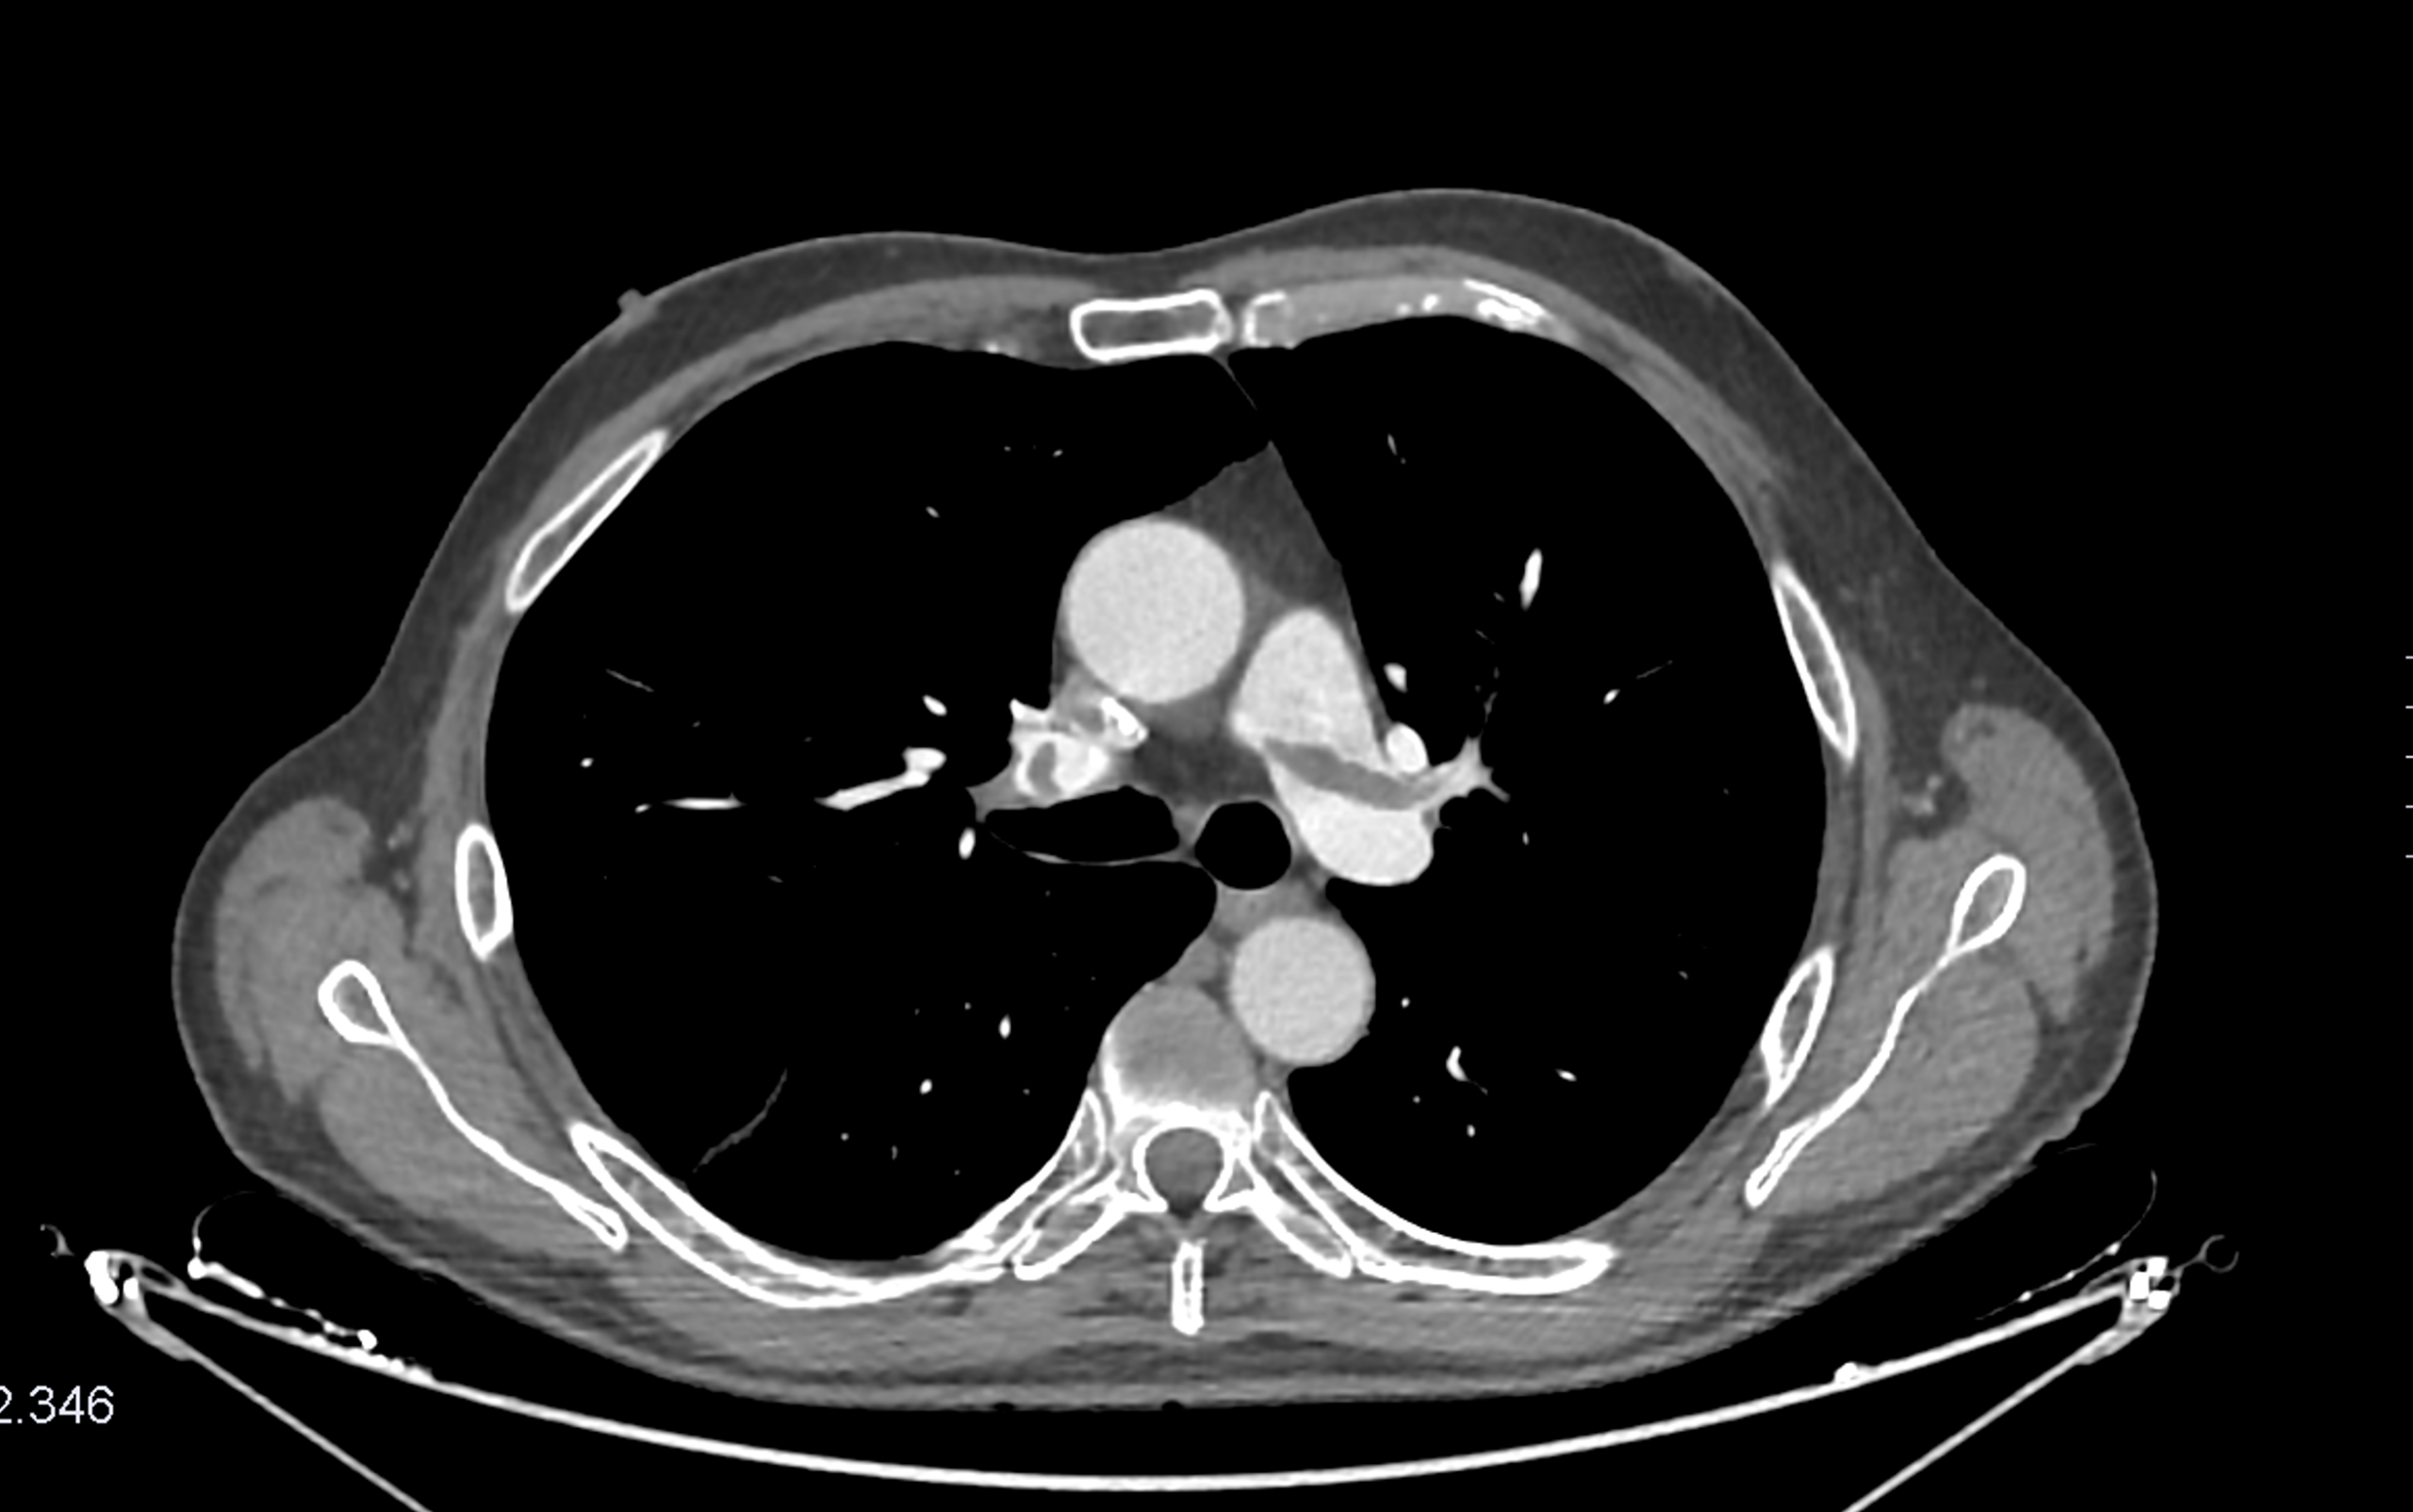

Angio-TC torácico con contraste i.v.